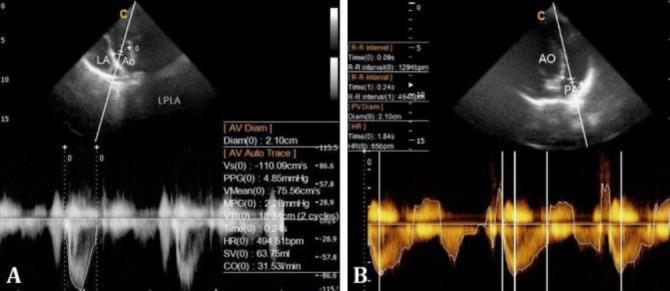

Echocardiography is a noninvasive, highly sensitive method for evaluating heart disease in veterinary medicine, crucial for measuring cardiac structures and functions. Despite its importance, limited data exist on sheep, particularly the Ghezel breed, a significant breed in Iran. This study aimed to establish normal echocardiographic values for Ghezel sheep, providing reference data for both clinical and research applications. We evaluated 15 healthy Ghezel sheep with a mean age of 16.50 ± 1.80 months and a mean weight of 42.69 ± 4.73 kg. Comprehensive clinical exams, biochemical and hematological tests and color Doppler echocardiography were performed. Descriptive results from standard right and left parasternal views in both longitudinal and transverse planes were obtained and compared to existing studies. The study successfully established pulse wave Doppler reference values for the Ghezel breed. These findings could be used in diagnosing heart disease in Ghezel sheep and would be beneficial in future research particularly in sheep used as an animal model for translation in human cardiac studies.